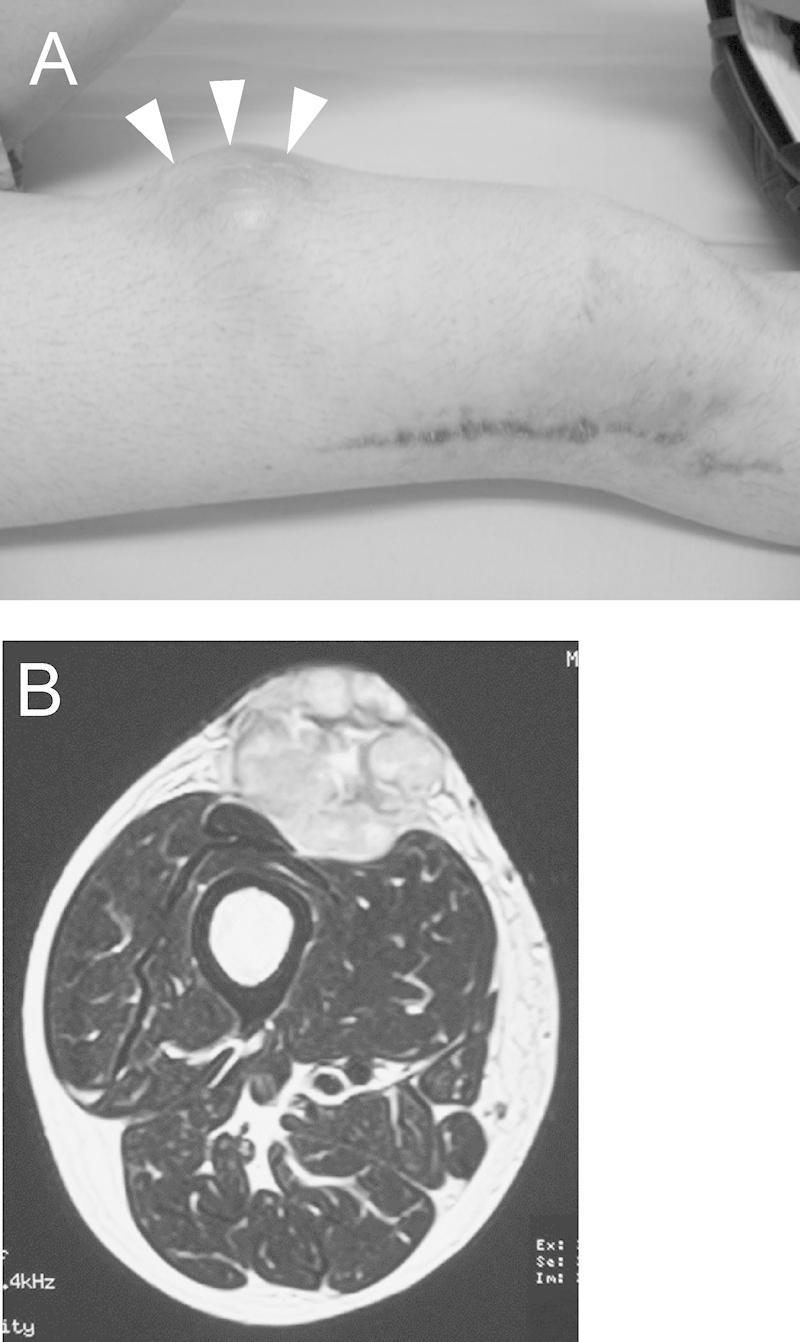

PRESENTATION OF CASE

Our current case showed a long-term benign course before the operation, although the subcutaneous tumor was larger than 10cm at presentation. The SFT was diagnosed by needle biopsy, and wide resection was performed. Histological findings showed proliferation of capillaries surrounded by masses of spindle-shaped cells without any cytologic atypia, and the percentage of MIB-1-positive nuclei was 2.1%. However, a rapidly enlarging recurrent tumor was observed 11 months after the operation. A second wide resection for the recurrent tumor was performed. Histologically, the tumor cells uniformly displayed significant cytologic atypia and pleomorphism, and had 40-50 mitoses per 10 high-power fields. The proportion of MIB-1-positive nuclei was 48%. Consequently, the tumor was diagnosed as a SFT with malignant transformation.

我们描述了一例罕见病例,一名31岁男性大腿部出现一例组织学分级均为高级别的恶性孤立性纤维瘤(SFT),在广泛切除术后复发。

病例介绍

我们的当前病例在手术前呈现出长期的良性病程,尽管皮下肿瘤在初诊时大于10cm。通过针吸活检诊断为SFT,并进行了广泛切除。组织学检查结果显示,毛细血管在梭形细胞团块周围增生,无任何细胞学异型性,MIB-1阳性核的百分比为2.1%。然而,术后11个月观察到肿瘤迅速复发且增大。对复发性肿瘤进行了第二次广泛切除。组织学上,肿瘤细胞均表现出明显的细胞学异型性和多形性,每10个高倍视野有40 - 50个有丝分裂象。MIB-1阳性核的比例为48%。因此,该肿瘤被诊断为发生恶性转化的SFT。